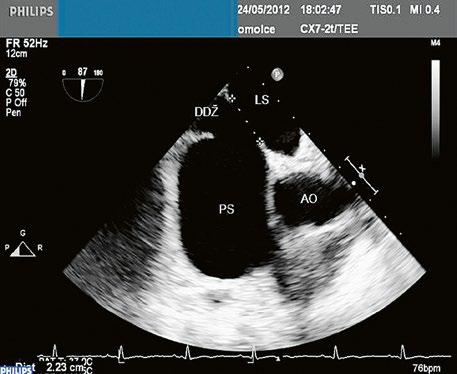

Obr. 45.1 Defekt septa síní typu II v TEE

AO – aorta, DDŽ – ústí dolní duté žíly do pravé síně, defekt septa síní je označen křížky, má předozadní průměr 22 mm, zasahuje blízko zadní stěny levé síně, LS – levá síň, PS – pravá síň

z Defekt síňového septa typu secundum: 70 % všech komunikací na úrovni síní, v místě fossa ovalis, s možnou extenzí ke stěnám levé síně (Obr. 45.1, Obr. 45.2, Video 45.1, Video 45.2).

Obr. 45.2 Defekt septa síní typu II v TEE

AO – aorta, ASD – defekt septa síní typu secundum označen šipkou, zelenými křížky je označen malý přední rim k aortě, LS – levá síň, PS – pravá síň